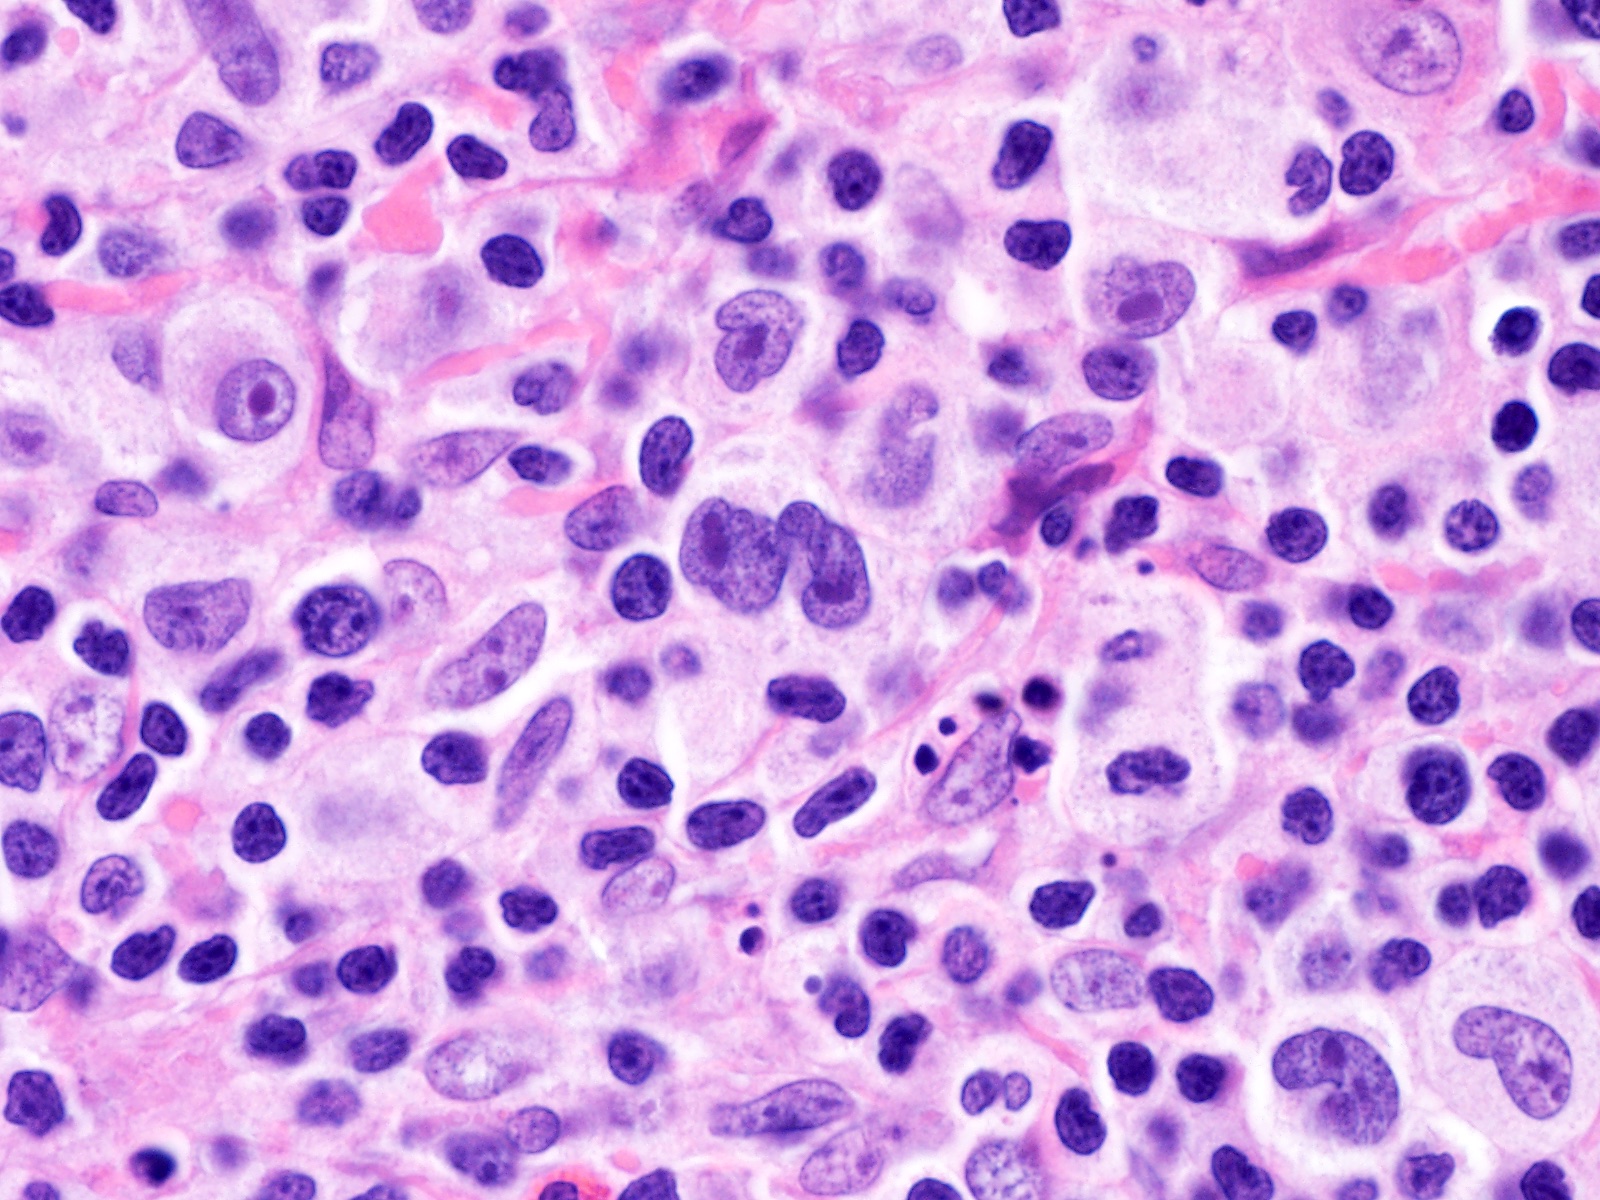

Disease Processes & Lesion Recognition

Examine each slide systematically — architecture first, then cellular detail — before reading the annotated lesson notes.